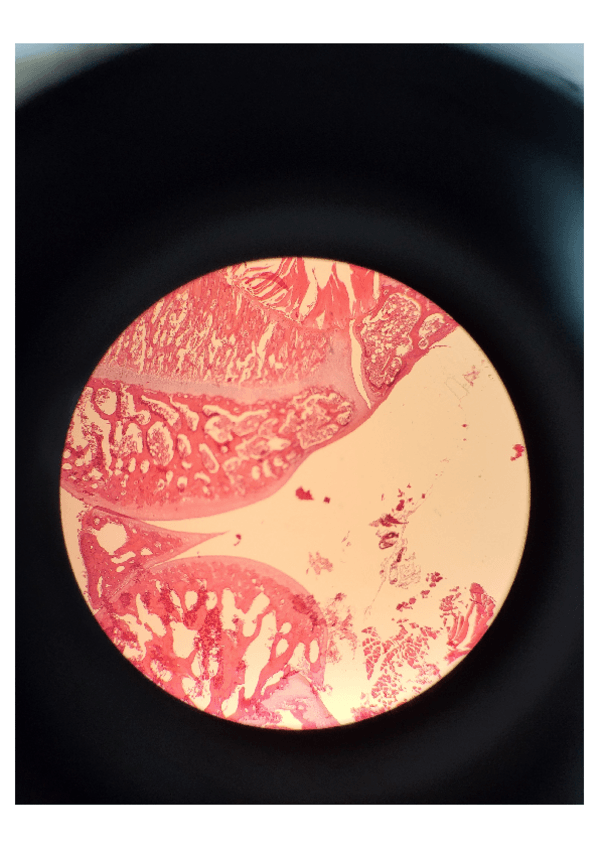

En el documento, se encuentran explicadas las imágenes para comprenderlas bien. Además de esto, en algunas muestras se incluye un recuadro en el que aparece lo que hay que poner en el examen, según dijeron los profesores durante las prácticas.

He publicado nuevos practicas de 1º Histología Médica I: Portafolio-Practicas-Histologia.pdf

He publicado nuevos practicas de 1º Histología Médica I: Imagenes-Practica-5-Histologia-1.pdf

He publicado nuevos practicas de 1º Histología Médica I: Imagenes-Practicas-3-4-Histologia-1.pdf